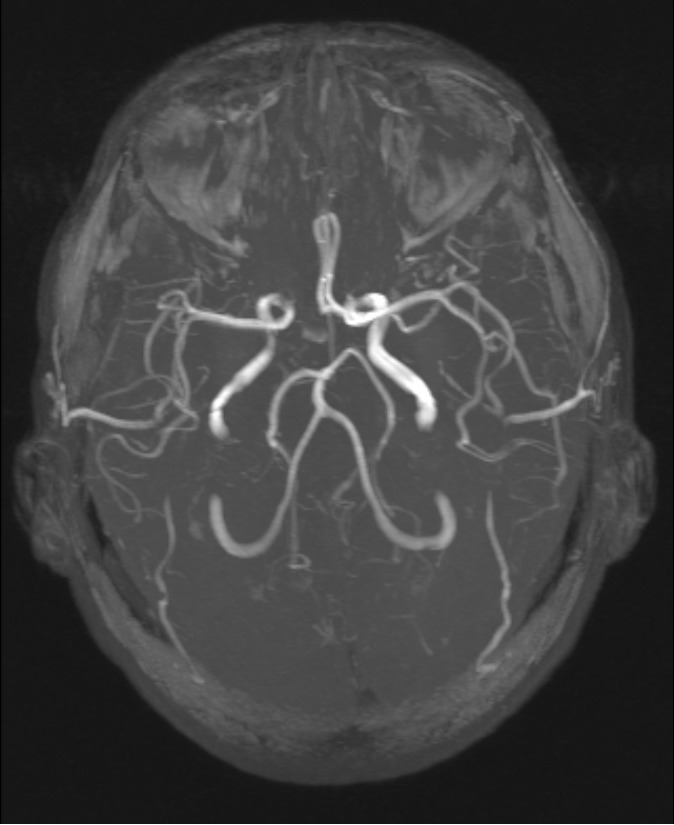

МРТ сосудов головного мозга – это одна из лучших современных методик диагностики, которая в своей точности, чувствительности и специфичности превосходит компьютерную томографию и рентгенографию. Благодаря этому подобное исследование активно используется для первичного выявления и контроля уже обнаруженных заболеваний.

МРТ сосудов мозга позволяет максимально детально исследовать сосуды. С помощью данного диагностического мероприятия возможно узнать самую важную информацию о качестве кровообращения в головном мозге. Нередко это позволяет своевременно начать лечение или принять срочные леченые меры (при подозрении на инсульт).

Сразу следует отметить, что точность МРТ сосудов мозга во многом зависит от типа аппарата, на котором проводиться процедура. Лучше всего для этой цели применять современные высокопольные томографы с мощностью с 1, 5 Тесла от производителя Сименс. Именно они показывают наиболее точное состояние сосудов (с толщиной среза до 3-4 мм). Это позволяет увидеть даже мельчайшие изменения и первичные нарушения в тканях.

МРТ сосудов головного мозга с контрастом дает возможность оценить общее кровообращение в мозговых артериях. Также исследование способно выявить воспалительные процессы, аномалии строения сосудов, кровотечение, онкологическую патологию и прочие изменения.